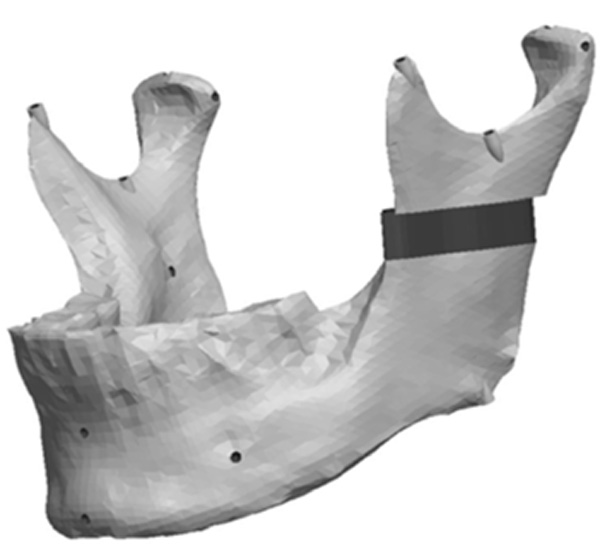

The Ramus section was located half way between the superior aspect of the condylar head and the depth of the antigonial notch. The location for the cut was determined by constructing a point half way between the most superior point on the condyle head (Cs) and the depth of the antigonial notch (Ag). A plane was selected perpendicular to the Cs-Ag line and plane MD which was used to guide the cut that penetrated through the neck of the condyle running parallel to the occlusal plane. Fig. (13) represents the location in the ramus of the mandible for the sections made to generate the ramus asymmetries. From this section, vertical and complex asymmetries were constructed in the ramal region. The vertical manipulation studied was to a maximum of 9mm asymmetry on 3mm increments and the complex ramal asymmetry was maximum of 9mm vertical with 3mm increments and 6mm horizontal lateral asymmetries with 2mm increments Fig. (14) and Fig. (15) represent images of models with the vertical ramal asymmetry and with the complex vertical and horizontal lateral ramal asymmetry respectively.